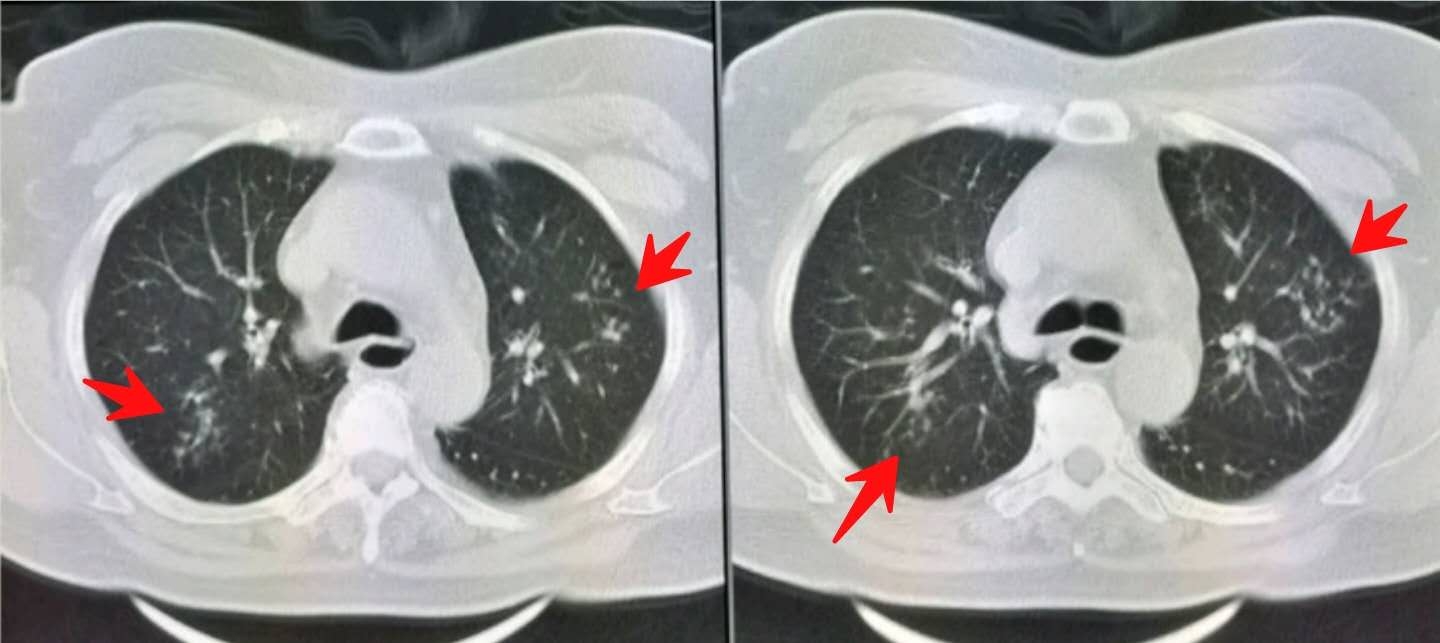

胸部CT发现双肺多发小斑点状影,提示沿支气管扩散的肺内炎症。

同时我们注意到她的食管下段扩张(绿色圈):

建议给她预约个食管镜检查,最终明确为胃食管反流,并反流性食管炎。